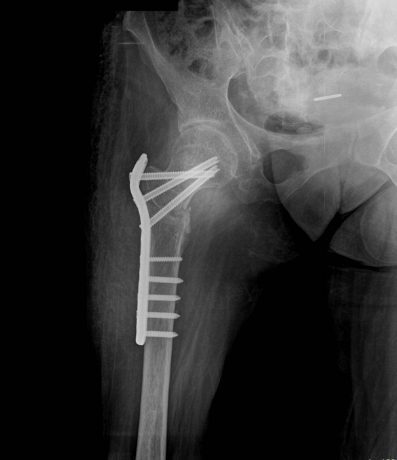

小兒麻痺症圖片

小兒麻痺 (7)

小兒麻痺 (8)

小兒麻痺 (9)

小兒麻痺 (57)

小兒麻痺 (58)

小兒麻痺 (59)

小兒麻痺 (6)

小兒麻痺 (60)

小兒麻痺 (61)

小兒麻痺 (62)

小兒麻痺 (54)

小兒麻痺 (55)

小兒麻痺 (56)

小兒麻痺 (5)

小兒麻痺 (50)

小兒麻痺 (51)

小兒麻痺 (52)

小兒麻痺 (53)

小兒麻痺 (39)

小兒麻痺 (4)